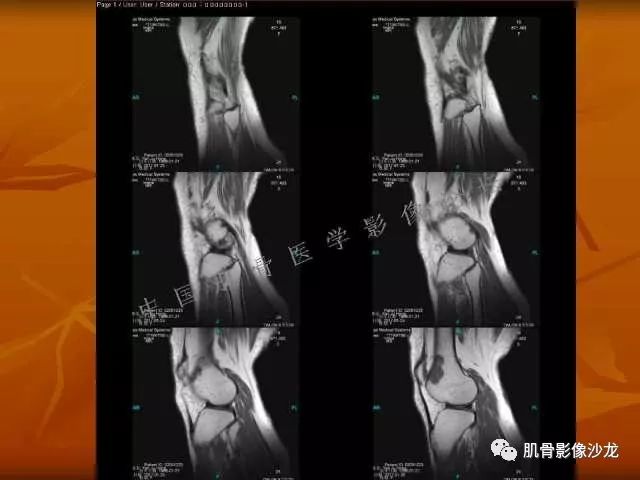

西门吹雪 :股骨下段,偏侧破坏,长T1混杂T2,移行带较窄,但局部边缘欠规则。周围骨髓水肿不明显,软组织结构清晰,T2病变上部片状低信号 , 膨胀不明显。

阳光明媚 :股骨远端前部可见片状长T1、长T2不均信号影,压脂序列呈不均高信号影,平片无明显钙化,边界清。内有纤维、粘液,

雪舞 : 股骨下端,皮质下偏心性溶骨性破坏,分叶状,T2混杂高信号。无明显软组织肿块。X片未见异常。

飞鹰行动 : 第一列可以看见T2小结节样高信号,周围有纤维组织环绕

高回青 : 另外还可以见到扇贝状分叶

2、软骨基质T2WI高信号,软骨小叶分叶状,也就会出现高老师提到的骨内膜扇贝形压迹。一般认为骨内膜扇贝形压迹超过骨皮质厚度的2/3是软骨肉瘤在长管状骨的特征性表现。如上图。3、软组织肿块或肿胀;